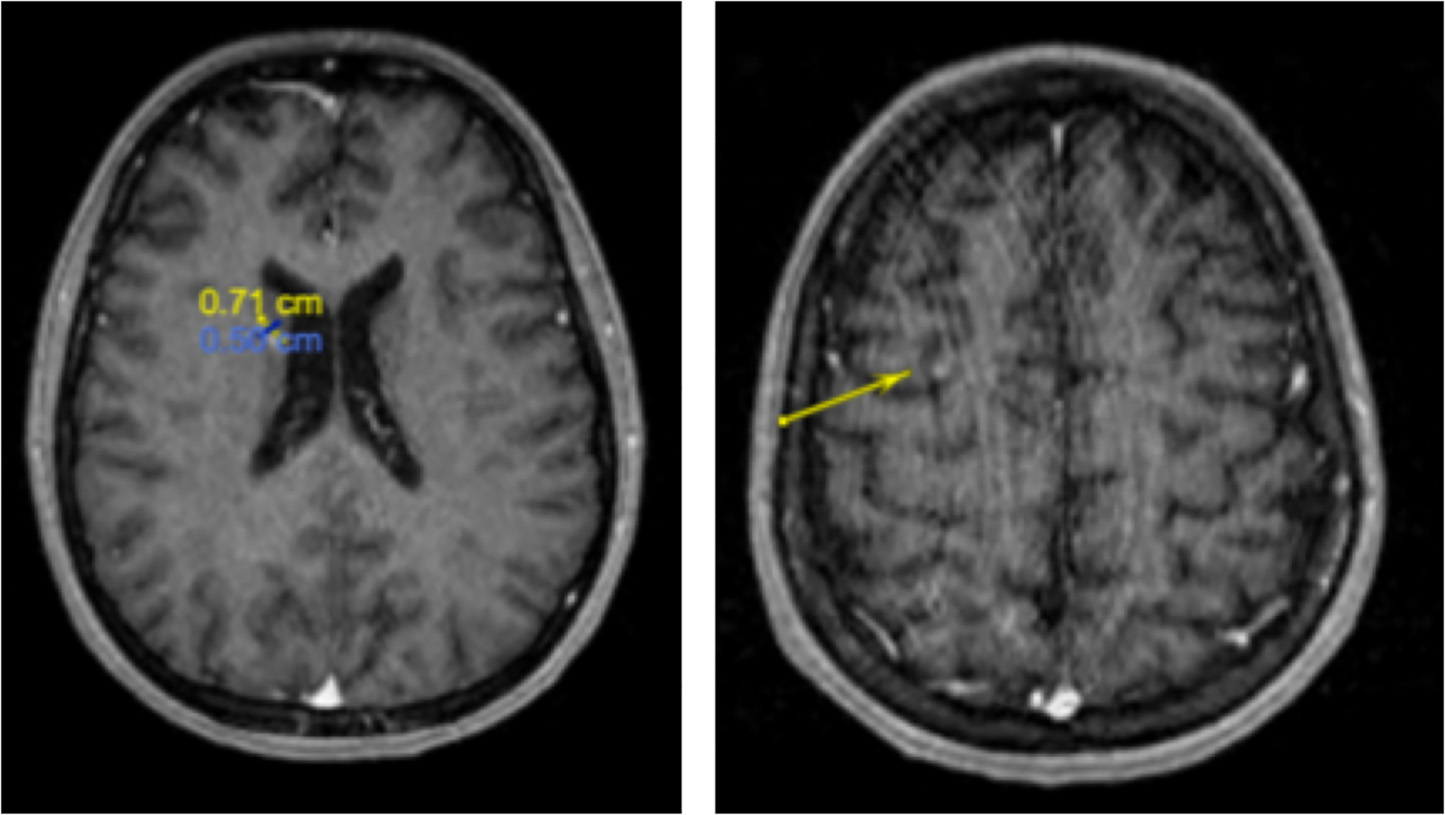

和上腔静脉综合征。MRI和CT扫描的进一步分期显示转移至其右侧脑尾状核和右肝后外侧叶(图7、8)。患者开始接受放射治疗,但在接受了两次纵隔肺部肿块的放疗后,决定停止放疗,因化疗后症状迅速改善,仅继续化疗。7月开始使用阿来替尼3个月后,该患者几乎无症状,氟脱氧葡萄糖

PET扫描显示改善,包括肺实变明显减少但仍持续存在的胸腹部淋巴结病变,淋巴结转移和双侧胸腔积液消退。

图7 MRI扫描显示右尾状核(左图,7 x 5毫米)和右额叶上部(右图,箭头)出现增强的转移病灶。